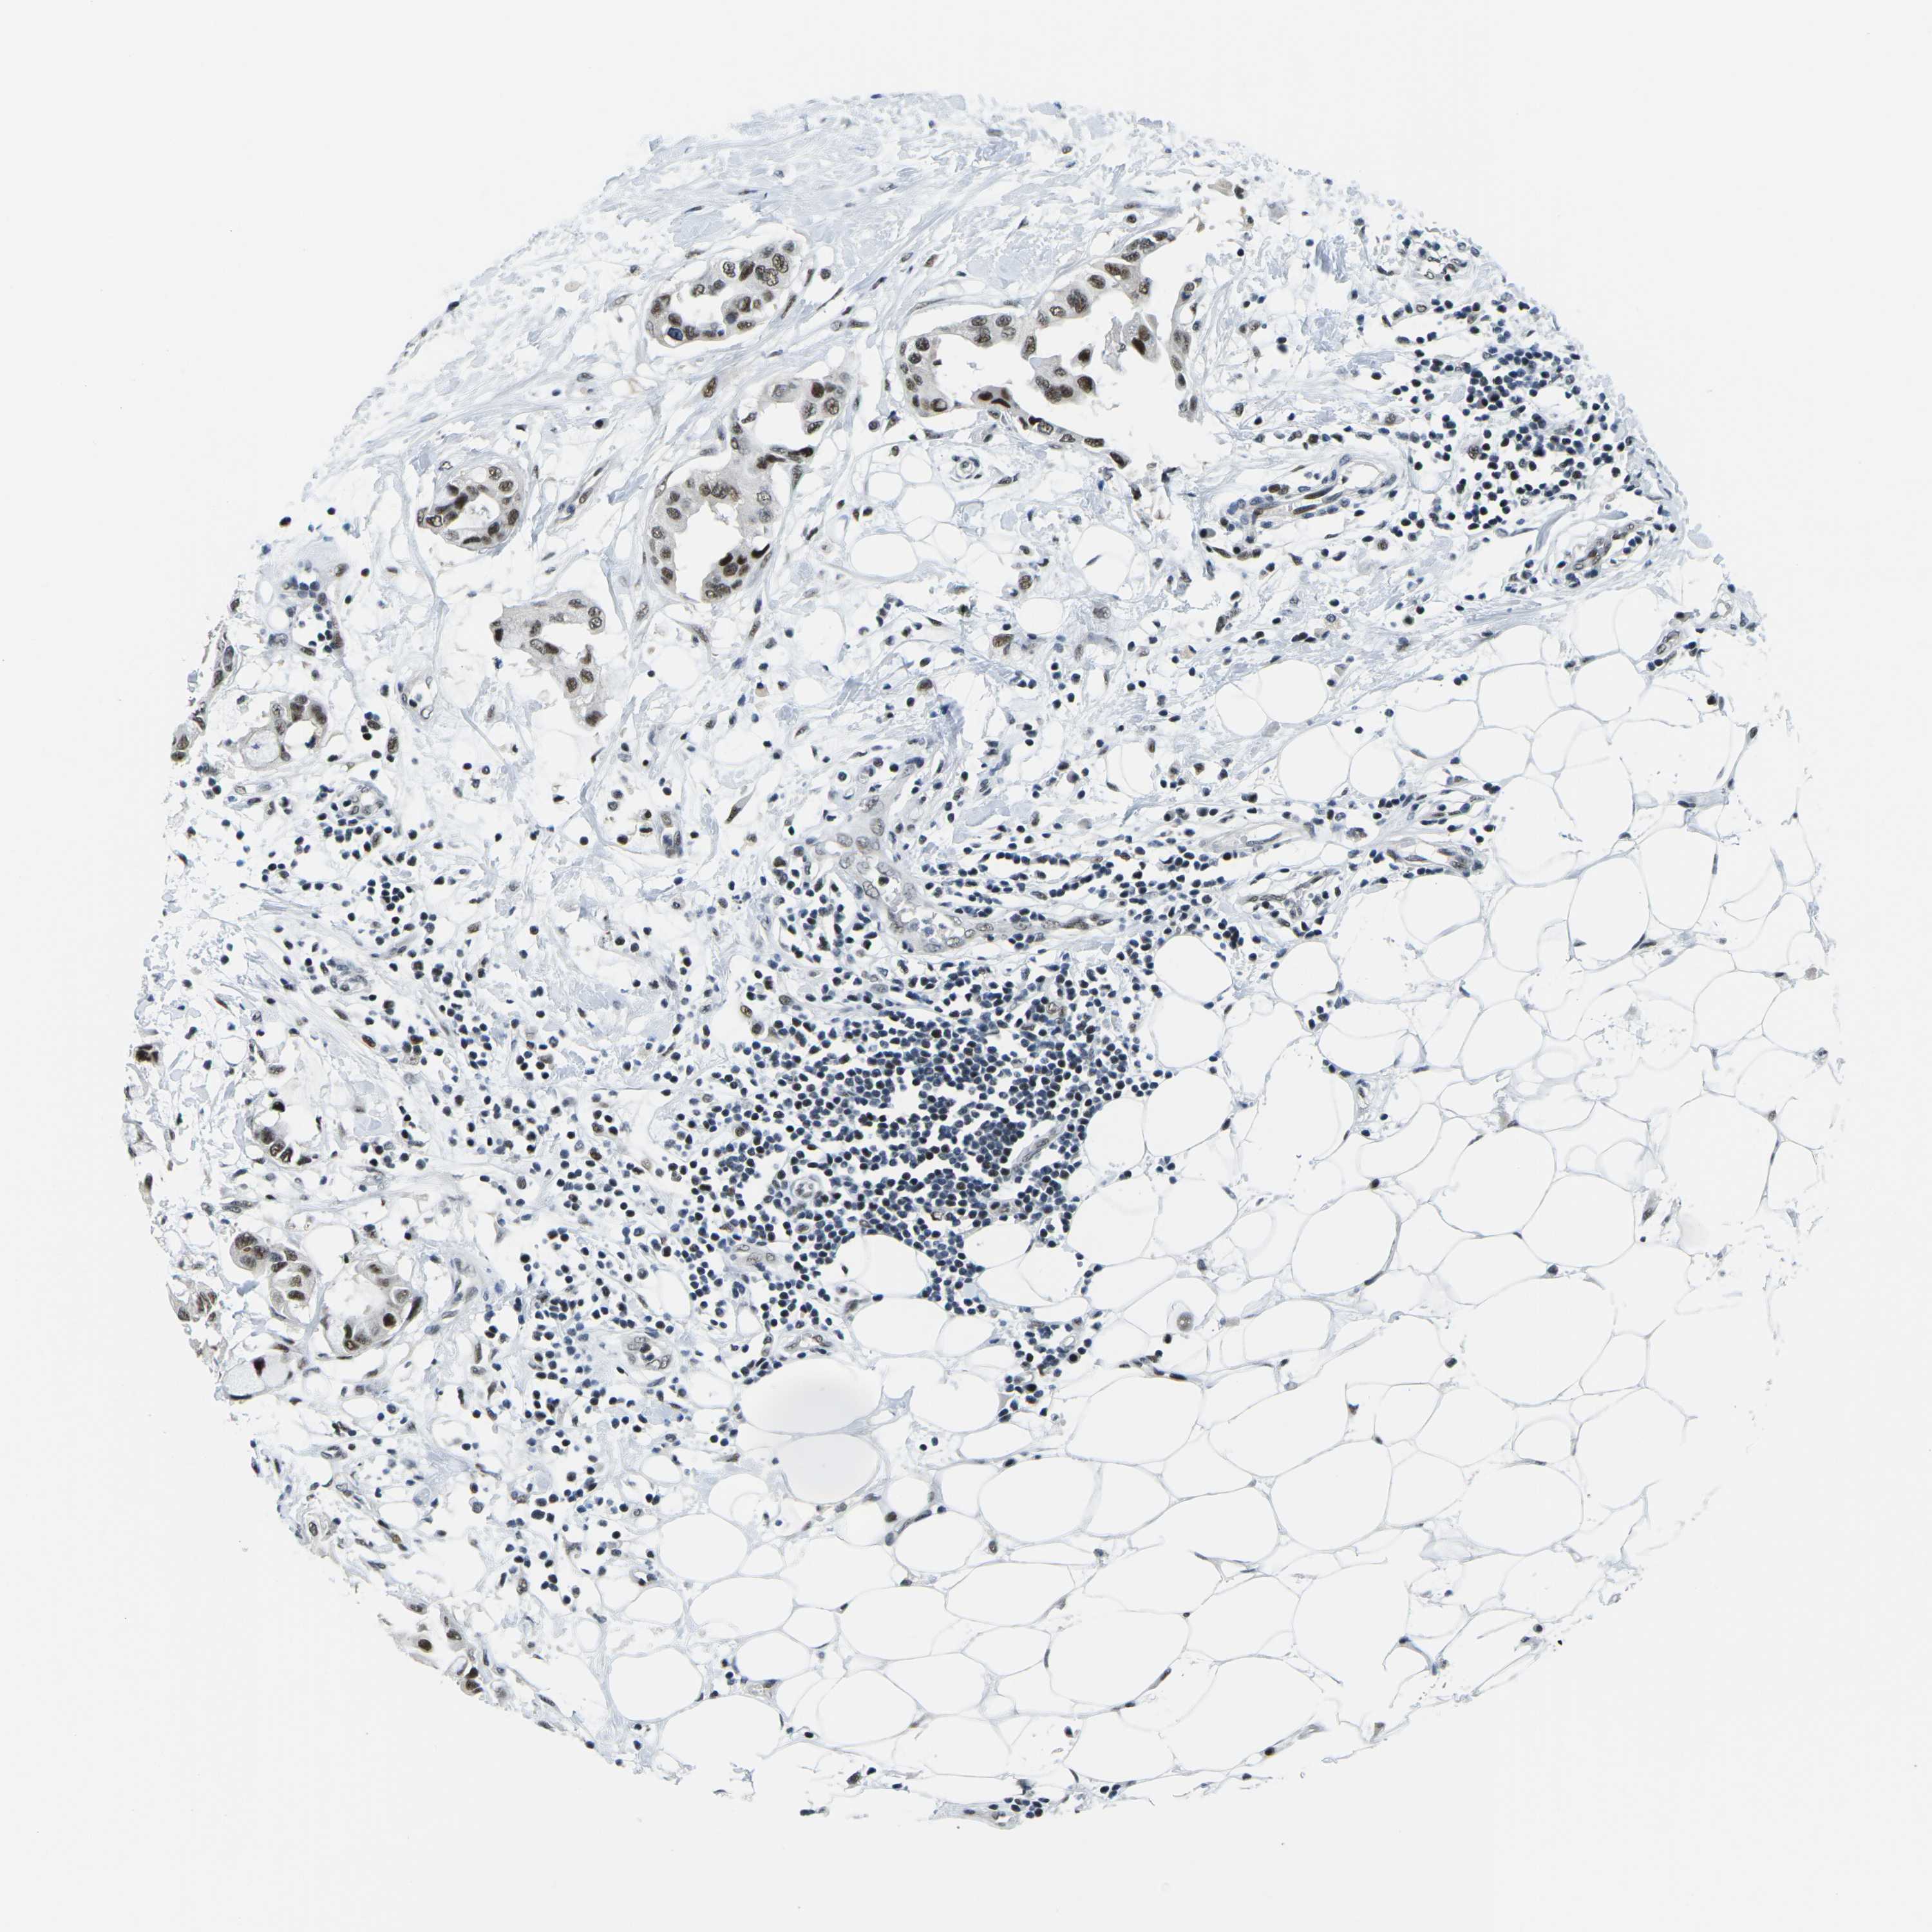

CANCER BREAST CANCER Show tissue menu

BRCA TCGA BRCA VALIDATION PROTEIN EXPRESSION